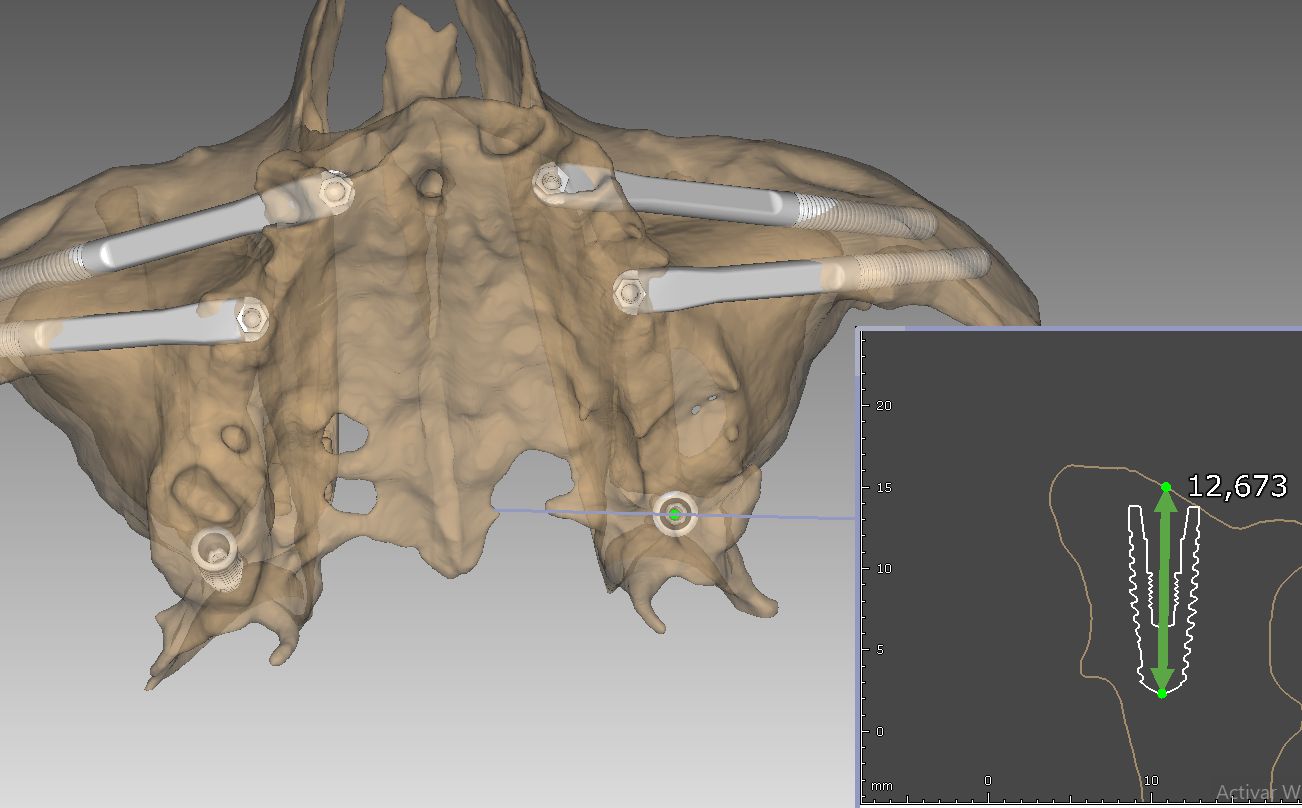

Cada paciente presenta una anatomía única. Por ello, en nuestra clínica de Soria, realizamos un estudio tridimensional para determinar qué combinación de implantes es la adecuada:

1. Implantes Cigomáticos

Son implantes más largos que se fijan en el cuerpo del hueso cigomático (pómulo). Son la «regla de oro» para tratar maxilares totalmente atróficos. Permiten colocar una arcada completa de dientes fijos sin necesidad de realizar injertos de cadera o calota craneal, reduciendo drásticamente la morbilidad del paciente.

3. Implantes Transnasales

Es una técnica innovadora donde el implante atraviesa una pequeña porción de la cavidad nasal para anclarse en hueso duro opuesto. Se utilizan en casos muy específicos para ganar estabilidad en la zona anterior del maxilar cuando el hueso es inexistente.

- Planificación digital y cirugía guiada para máxima precisión.